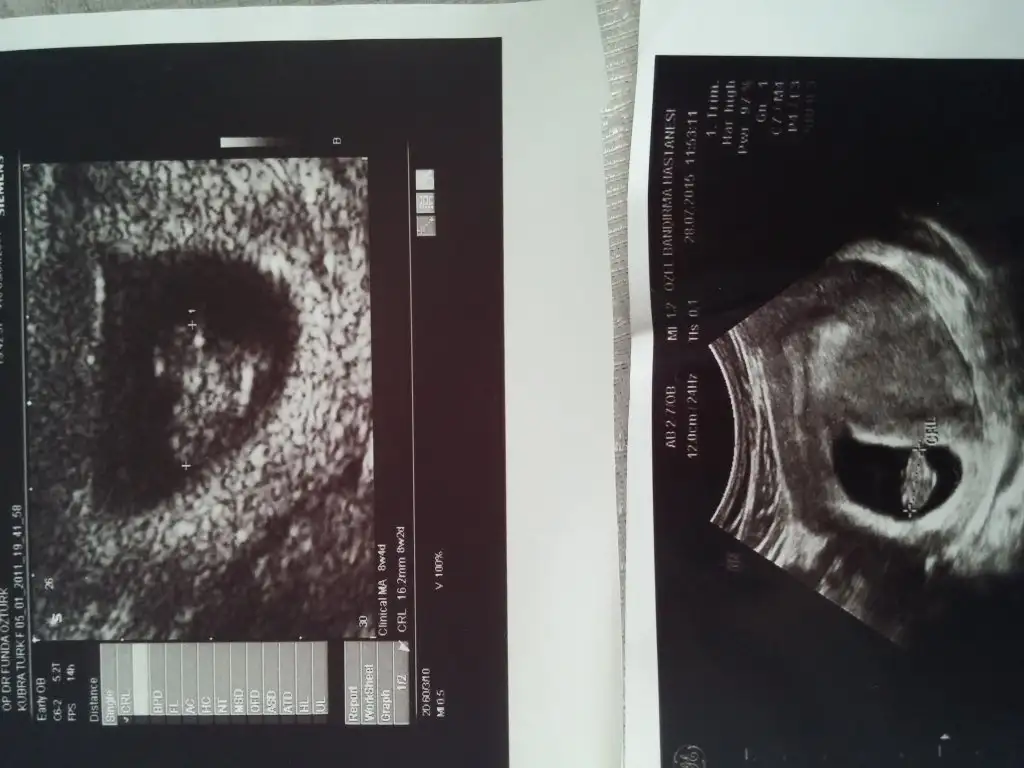

P_20150907_120448.webp